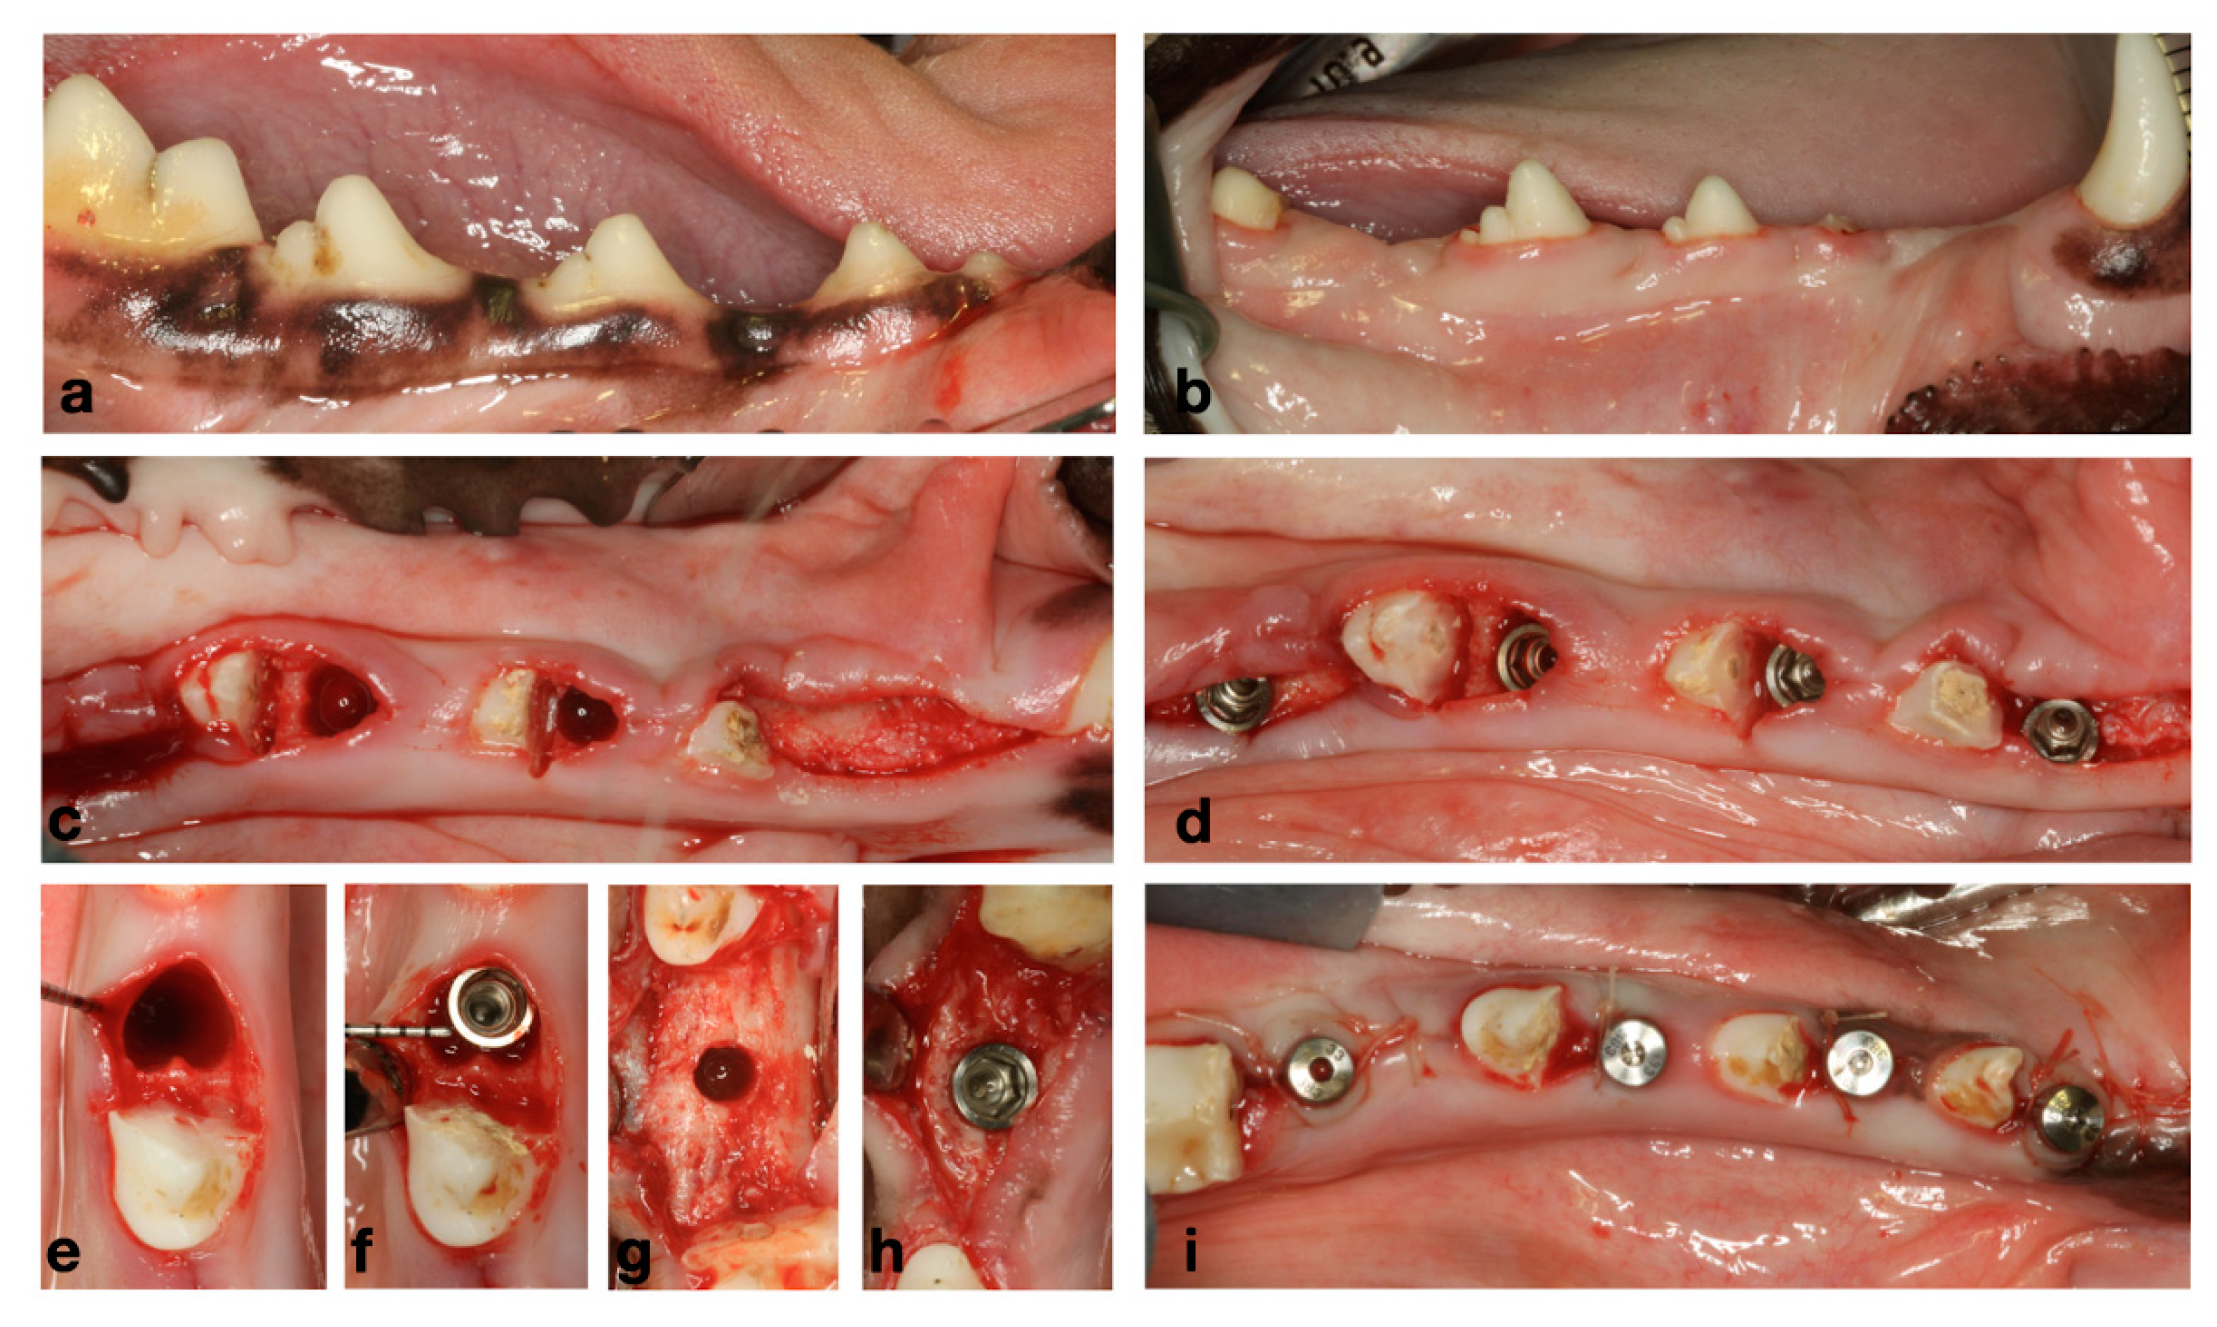

The study evaluated two surgical implant placement protocols, delayed and immediate (control and test groups, respectively) at two healing periods, 2 and 8 weeks (Figure 1). The detailed description of the experimental model has been previously reported [17]. In brief, the first intervention consisted of the extraction of first premolar (P1) and the mesial roots of the second premolar and first molar (P2 and M1) in one hemimandible. After a healing period of 2 months, implants were placed in these healed ridges (control sites; M1 and P1), while the remaining roots were extracted, and implants were placed immediately in these fresh extraction sockets (test sites—P3 and P4) (Figure 2a). The same surgical intervention was repeated on the other hemimandible 6 weeks after (Figure 2). After 2 weeks of healing following the last surgery, the animals were euthanized, providing therefore one hemimandible with a healing period of 2 weeks, while the contralateral hemimandibles provided 8 weeks healing samples. All subjects successfully completed the study protocol with no reported adverse events.

Figure 2.

(a) Baseline clinical situation. (b) Healed ridges after 2 months of healing from initial extractions. (c) Flapless extraction of messiah roots of P3 and P4. (d) Immediate and delayed implant placement. (e,f) Immediate implant placement. (g,h) Delayed implant placement. (i) Healing abutments and transmucosal healing.